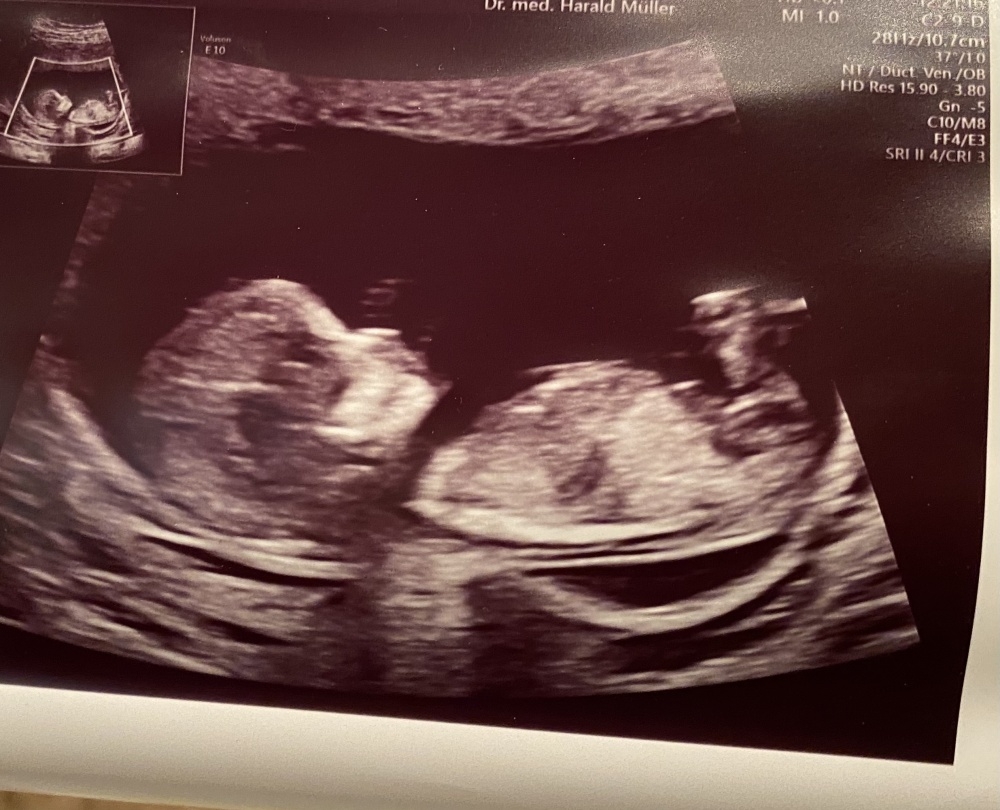

War Montag beim Arzt (SSW 20) und habe eine Tendenz bekommen. Mich würde interessieren, was ihr Profis dazu sagt, ich kann da ja leider absolut nichts rauslesen Bin gespannt, was ihr sagt und ob es sich mit der Tendenz meiner Ärztin gleicht